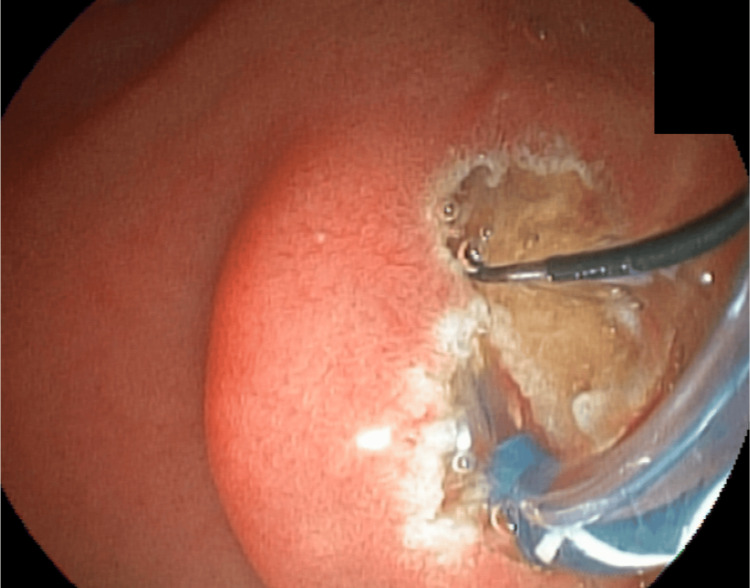

After this new dilation, the removal of the incarcerated set was attempted using mouse tooth forceps. However, no success was noted. An 8.5-French biliary plastic stent was placed (Figure 10).

The endoscopist then recommended a later endoscopic approach, removing the basket, stone, and prosthesis. However, the surgeon of the case opted for open surgery two days later and cholecystectomy, removal of the prosthesis, stone, and basket by duodenotomy, and CBD opening (Figure 11).